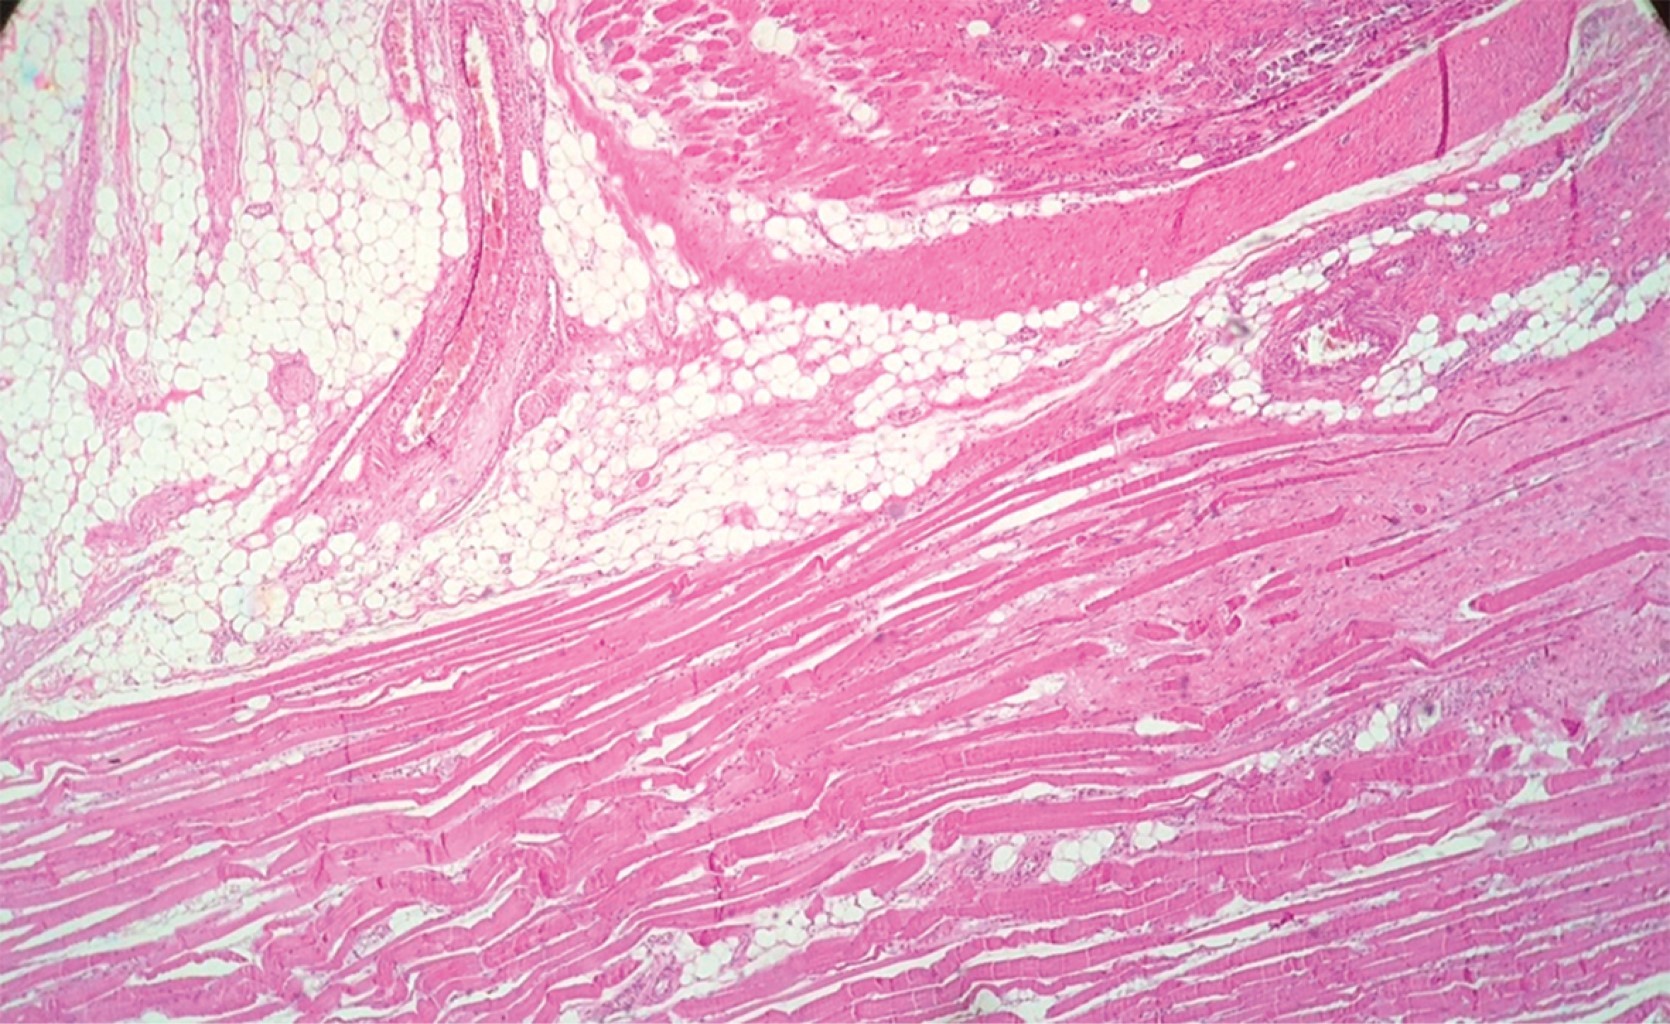

The histology report described a neoplasia with the anterior surgical edge in contact with the tumor. The rest of the margins were tumor-free and respected the subclavian vein and artery. The definitive histology report histologically described a non-atypical cellular proliferation, without evidence of mitosis, with spindle-shaped proliferating elements with intercellular collagenization and infiltrating adipose and muscular tissue in the periphery (Figures 4, 5 and 6).